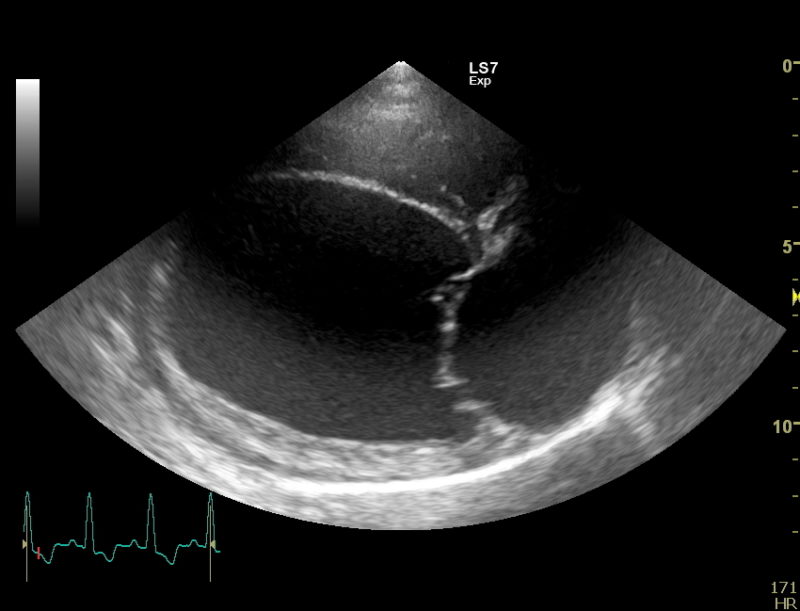

Weitergehend haben wir dann eine Herzultraschalluntersuchung durchgeführt um weitere Informationen über die zugrundeliegende Erkrankung zu bekommen. Auch in der Echokardiografie stellte sich das Herz deutlich zu groß da. Die linke Hauptkammer und der linke Vorhof sind massiv volumenüberladen, also mit zu viel Blut gefüllt. Durch die starke Blutfülle im Herzen hat sich auch der Klappenapparat der Mitralklappe aufgedehnt, sodass dieses Rückschlagsventil zwischen der linken Kammer und dem linken Vorhof nicht mehr richtig abdichtet. Resultat ist eine Mitralklappeninsuffizienz, die bei jedem Herzschlag etwas Blut in den linken Vorhof zurückfließen lässt. Der linke Vorhof wird, wie hier bei Faust sehr groß und das Blut staut in den Lungenkreislauf zurück, es entsteht ein Lungenödem. Vereinfacht gesagt Faust hat „Wasser auf der Lunge“, eine weitere wichtige Ursache für Husten bei unseren herzkranken Hunden. Die Herzmuskulatur bei Faust ist eher dünn und die Pumpkraft (Kontraktilität) der Herzmuskulatur ist sehr schwach.

Daraus leitet sich die Diagnose ab: Faust hat eine dilatative Cardiomyopathie, DCM.

Dabei handelt es sich um eine primär zu schwache Herzmuskulatur. Der Herzmuskel pumpt nicht ausreichend kräftig genug und der Blutdruck des Hundes sinkt, der Körper reagiert und lagert mehr Flüssigkeit in den Gefäßen und dem Herzen ein und kann somit den Blutdruck zunächst wieder stabilisieren. Der Blutdruck sinkt aber bei nachlassender Kraft der Herzmuskulatur weiter ab und der Körper lagert noch mehr Blut und Flüssigkeit ein um den Blutdruckabfall zu kompensieren. Was kurzfristig gut gedacht ist, führt bei dieser Erkrankung langfristig durch diesen Teufelskreis zu einer massiven Größenzunahme des Herzens.